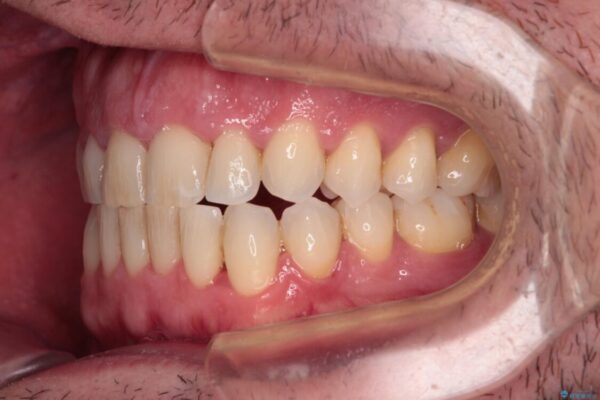

治療後について

舌のトレーニング自体は簡単なものですが、無意識下でも舌が突出しないようにしなければならないため、毎日継続することが最大の難関です。

時間はかかりましたがトレーニングを頑張ってくださり、無事に前歯を接触させることができました。

治療後